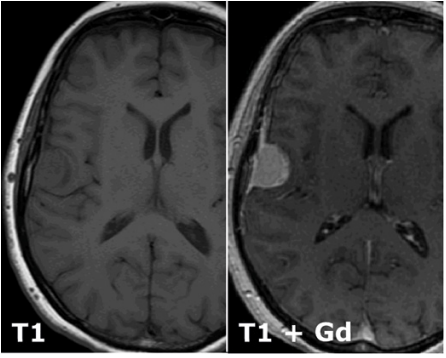

What is a T1 MRI scan and how does it differe from a T2 scan?

T2 is basically T1 but inverted.

T1 shows water dark

T2 shows water bright

Desribe what can be seen. What might it be, and which tissue might it derive from?

A meningioma of the right hemisphere deriving from meningiothelial cells.

Why does gadolinium enhance the lesion?

Gad enchances blood vessels and the tumour will be highly vascular

Which structures in the cerebral hemispehre is the lesion compressing?

The frontal lobe and the primary motor cortex